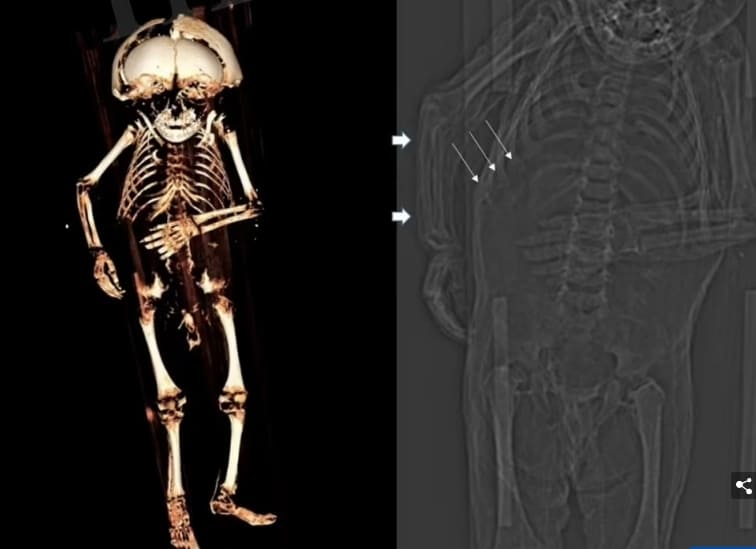

그의 몸은 폐렴과 비타민 D 결핍의 징후를 보여주는 CT 검사를 받았고, 방사성 탄소 연대 측정법은 그가 언제 죽었는지에 대한 다양한 날짜를 제공하기 위해 조직과 피부에 시행되었다.

오늘 Frontiers in Medicine에 발표된 이 연구를 위해, Nerlich 박사의 팀은 그의 치아를 연구했고 그의 뼈 길이를 측정했는데, 이것은 아이가 죽었을 때 12개월에서 18개월 사이였다는 것을 암시했다.

시신 해부 결과 아이는 남자였고, 머리카락이 검고 나이에 비해 과체중이어서 부모가 잘 먹일 수 있었던 것으로 나타났다.